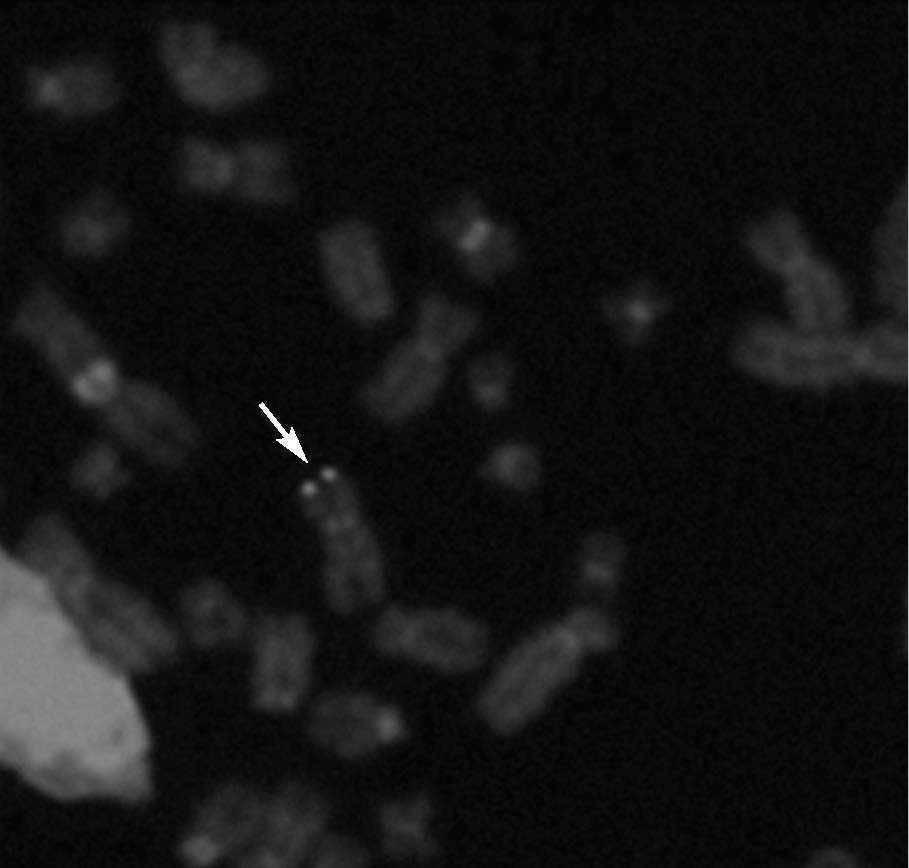

Hibridación fluorescente in situ (FISH)De 5 niños infectados congénitamente se examinaron muestras LCL de PBMC por FISH. Se detectaron señales positivas de FISH para HHV6 en 4 líneas celulares (fig. 2). Todas fueron del grupo de CI-HHV6, definido por la presencia de HHV6 en cargas virales elevadas en muestras de CBMC y folículos capilares. El único espécimen negativo era de un niño infectado congénitamente clasificado como TPI por bajas cargas virales en CBMC y ausencia de ADN de HHV6 en muestras de folículos capilares.

Fig. 2. Hibridación fluorescente in situ (FISH) representativa en cromosomas en metafase de un niño con elevados niveles de ADN de HHV6 en sangre de cordón (> 5 copias genómicas log10µg de ADN celular) y detección de ADN de HHV6 en sus folículos capilares. La flecha muestra señales simétricas de ADN de HHV6 en ambas cromátides de un único cromosoma.

La tasa de transmisión de CI-HHV6 no pareció estar afectada por la vía parental, igual que la proporción de niños con CI-HHV6 con herencia materna versus paterna no fue significativamente diferente, siendo sus cargas virales similares. No obstante, la variante A se detectó significativamente más a menudo en muestras sanguíneas de niños con CI-HHV6 que en muestras de niños infectados posnatalmente. Esto podría indicar que el HHV6A tendría una mayor propensión que el HHV6B a convertirse en cromosómicamente integrado en sitios cromosómicos específicos. Cada uno de nuestros pacientes con CI-HHV6 con muestras analizadas por FISH demostró integración simétrica de HHV6 al final de ambas cromátides de un único cromosoma. Muy pocos individuos o familias clasificados como CI-HHV6 habían sido analizados por FISH y sólo dos niños, ambos con problemas neonatales, fueron examinados durante la infancia14,17-19. La señal de integración de HHV6 en estos niños vino también de un solo homólogo de un cromosoma19. De los pocos cromosomas identificados con CIHHV6, los finales de los telómeros habían sido los sitios identificados predominantemente12,13,16-19,23. Teóricamente esto podría tener relevancia clínica puesto que los telómeros parecen ser integrales al mantenimiento de la función inmune normal37.